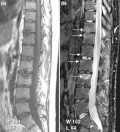

-

T2-weighted MRI (sagittal) of index finger in PsA (mutilans form) showing probable erosion (increased signal) at base of the middle phalanx (long thin arrow), synovitis at the proximal interphalangeal joint (long thick arrow), soft tissue edema (short thick arrow), and diffuse bone edema (short thin arrows) of the proximal phalanx. -